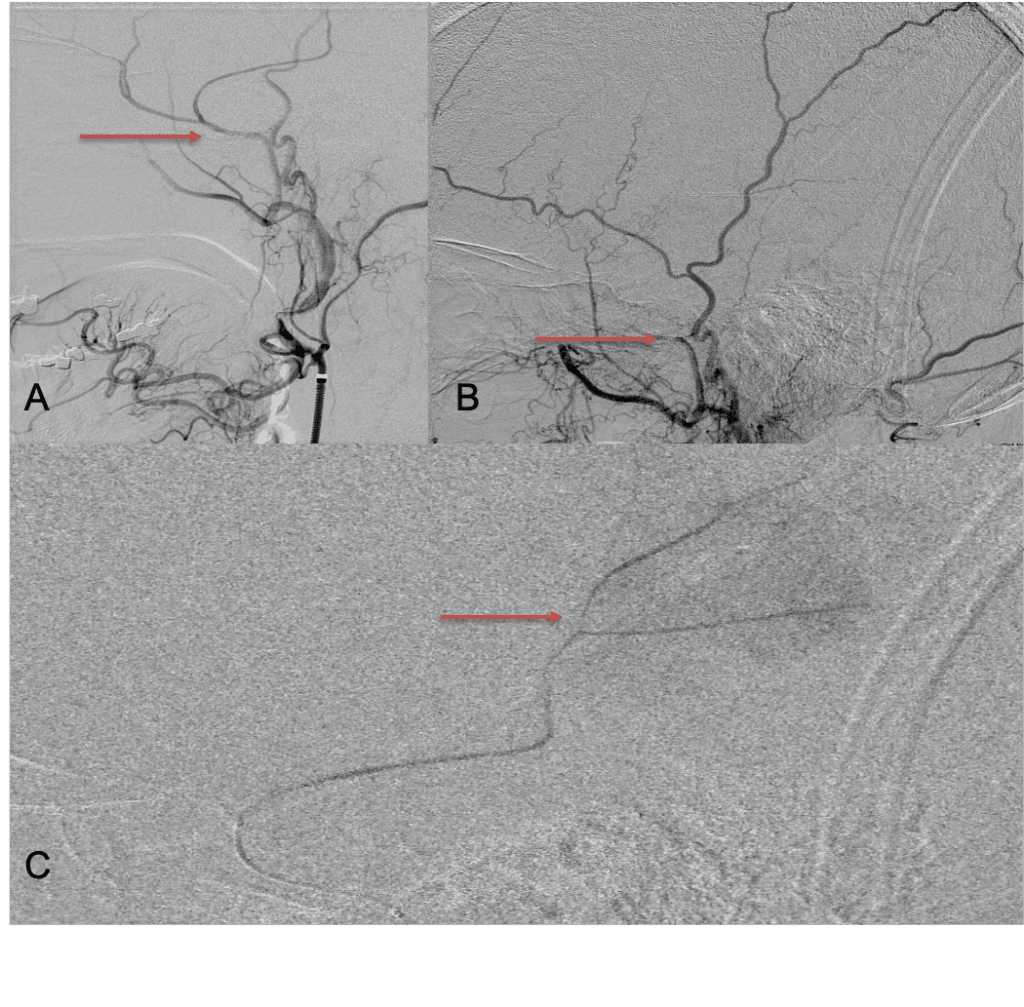

Although conventional surgical methods, such as burr hole irrigation or observation in asymptomatic or minimally symptomatic patients have been the mainstay of treatment, middle meningeal artery (MMA) embolization has emerged as a promising adjunctive or alternative treatment. MMA embolization is a neuroendovascular technique which involves placing a microcatheter into the Middle Meningeal Artery, most commonly on the side of the cSDH (occasionally, bilateral embolization has been recommended for larger or bilateral collection. Embolization of both the anterior (frontal) and posterior (parietal) division is performed using a variety of embolic materials (liquid NBCA, Onyx, coils), although polyvinyl alcohol particles of <250 microns are most commonly used to achieve distal penetration and occlusion of the pre-capillary and capillary beds. The micro-leakage of blood and transudative proteinaceous inflammatory fluid in these inflammatory membranes is creating an imbalance in cycle of resorption and preventing resolution or promoting recurrence or growth of these cSDH collections and associated mass effect and midline shift.

Figure 7. Neovascularized membranes within cSDH

Care must be taken to place the microcatheter within a safe position for embolization, with special attention to potential collateral branches to the orbit/eye via sphenoid or meningo-lacrimal branches (which may cause vision loss) or petrosal branches supplying the geniculate ganglion, the tympanic portion of the facial nerve, and often the trigeminal nerve via a branch coursing along the greater petrosal nerve. Once a safe position in the main trunk of the MMA, or superselectively in each of its divisions is achieved, embolization is performed until stasis of contrast and dense contrast staining of the dura is observed within the embolized vascular beds.7

Figure 8. Dense contrast staining of vascular membranes during embolization.